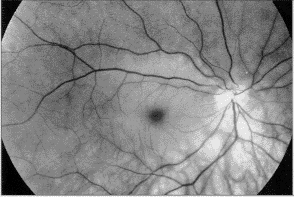

視網膜中央動脈阻塞(CRAO):常為篩板水平的粥樣硬化栓塞所致,系統性病因有偏頭痛、外傷、凝血障礙、炎症或感染性病、口服避孕藥、結締組織病包括巨細胞動脈炎等。視網膜脫離手術或眶內手術、下鼻甲或球後注射潑尼松龍等藥物偶有引起。表現為一眼突然發生無痛性完全失明。有的病人在發作前有陣發性黑曚。患眼瞳孔直接光反射消失,間接光發射存在。視網膜混濁水腫,尤其是後極部,但在中心凹,可透見其深面的脈絡膜桔紅色反光,在周圍灰白色水腫襯托下,形成櫻桃紅斑。視網膜動脈變細,少見視網膜出血。數周后,視網膜水腫消退,但視盤蒼白,視網膜萎縮,血管變細呈白線狀。治療應毫不遲緩,有數據顯示視網膜完全缺血後出現不可逆損害。

視網膜分支動脈阻塞(BRAO):血栓形成或栓塞是主要原因,系統性病因同CRAO。急性發作時眼底改變可不明顯,數小時後,受累動脈的供應區梗塞,視網膜呈灰白色水腫混濁。有時可見栓子阻塞的部位。視力可有不同程度下降,視野某一區域有陰影。數日後隨著血管再通和再灌注,水腫消退。遺留永久性視野缺損。後極部以外的阻塞,臨床症狀不明顯。治療上應尋找確定系統性病因,對因治療。